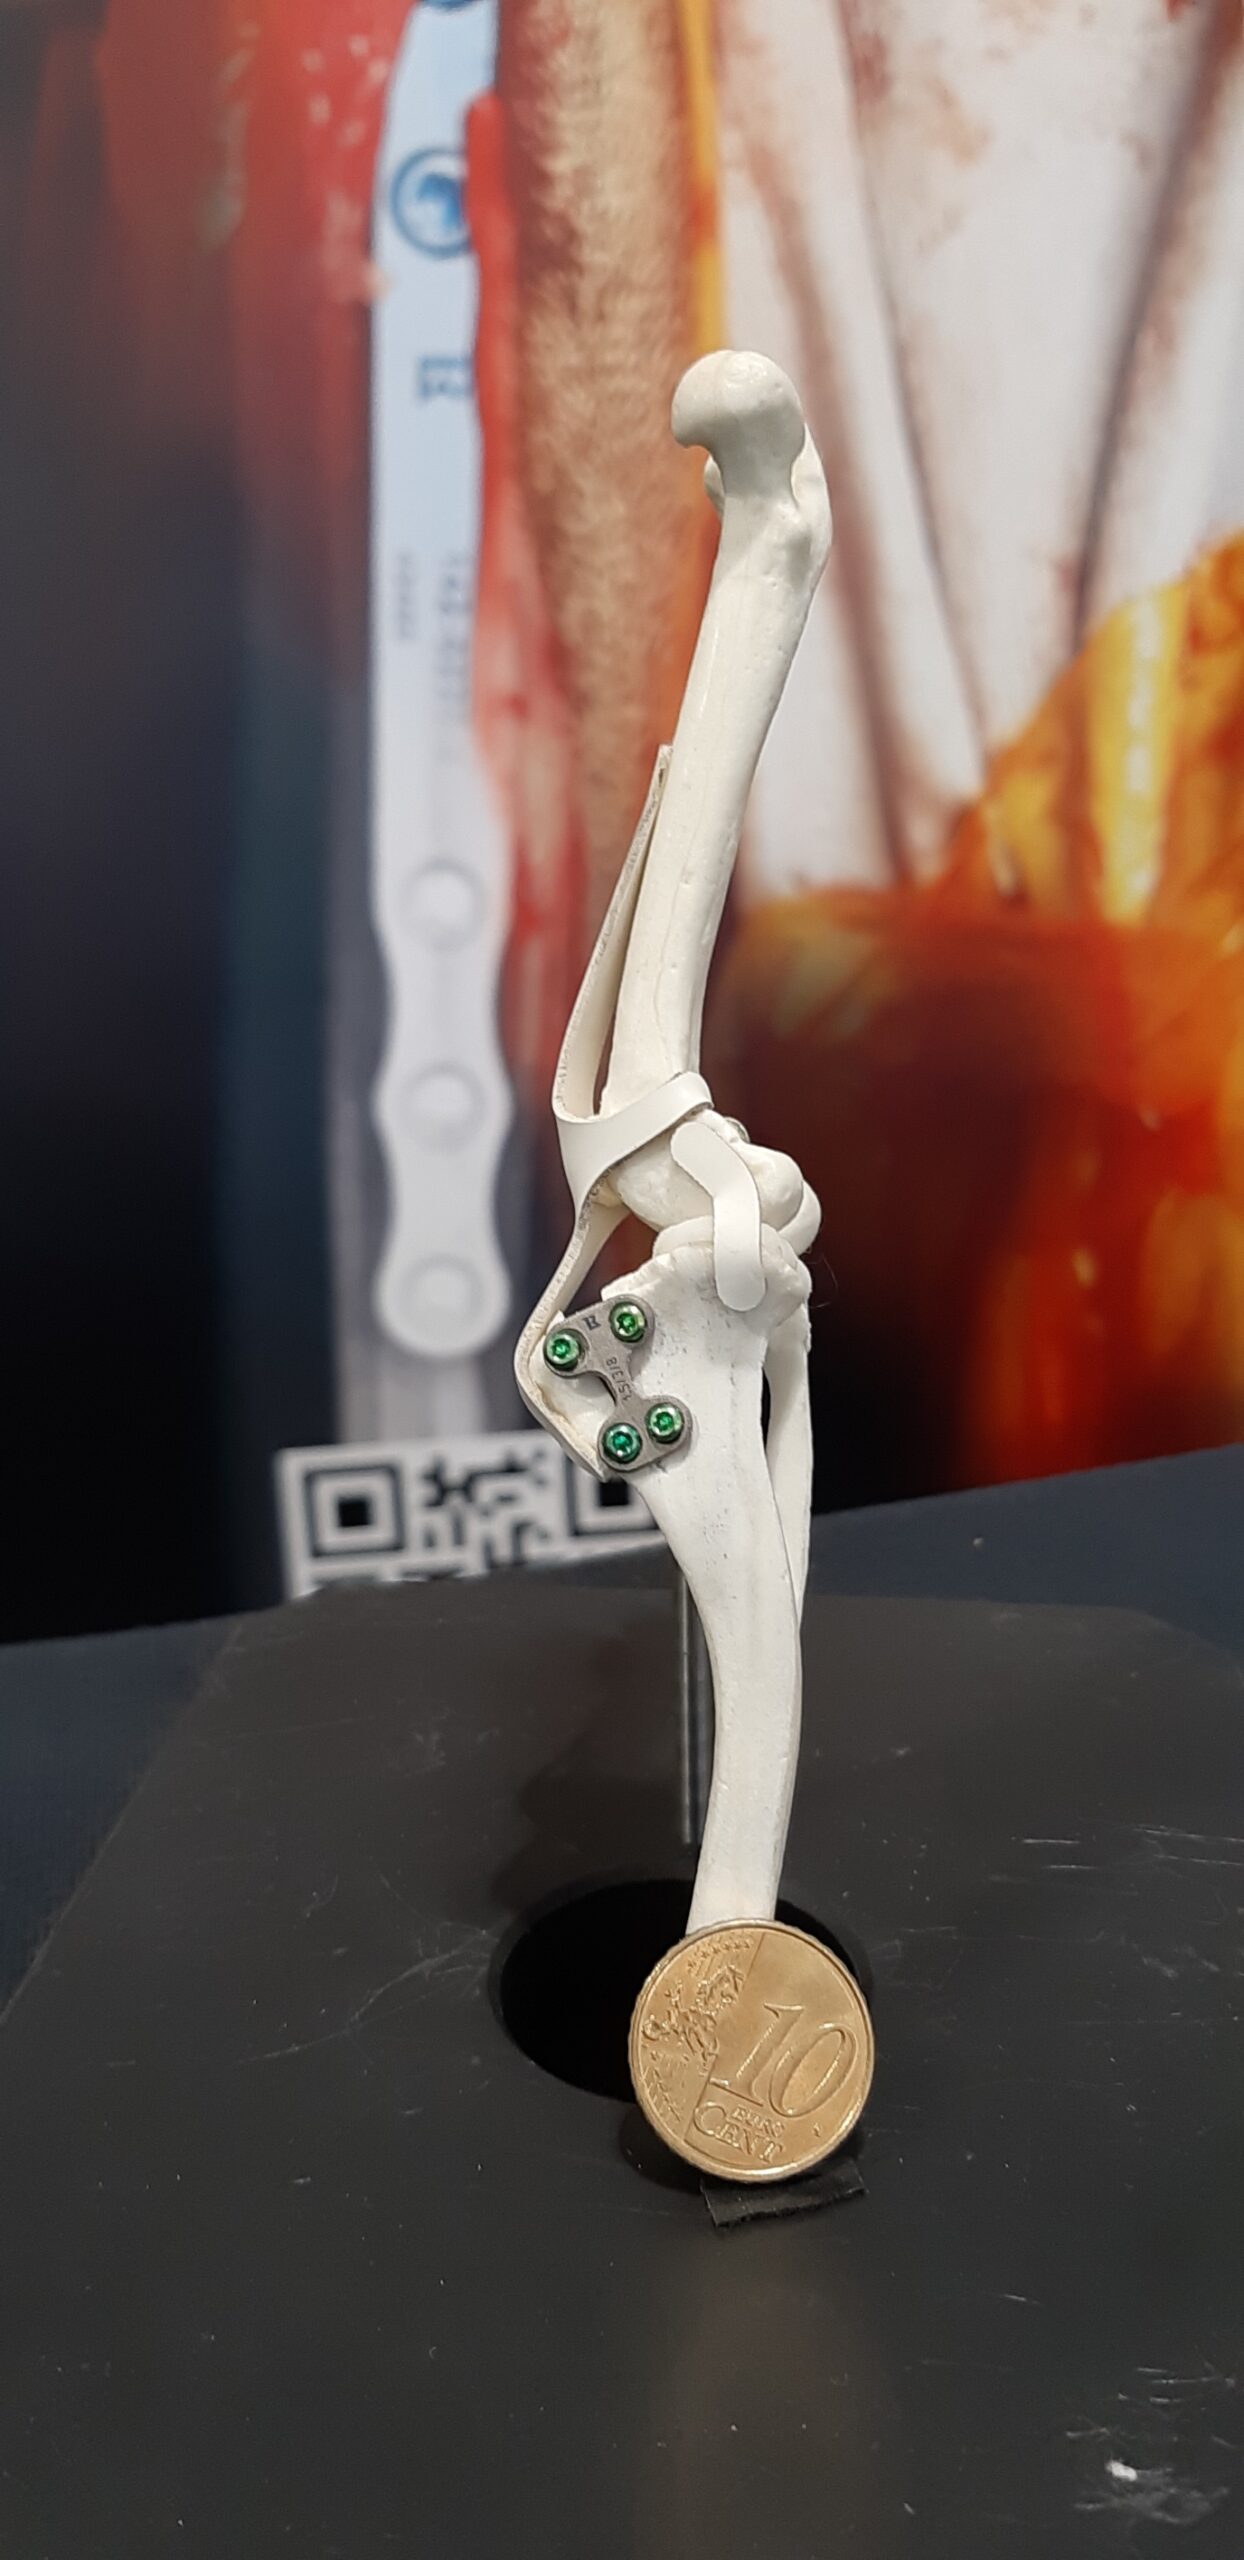

About Tiny TTA RAPID

Tiny TTA RAPID® is specifically designed for small animals, particularly cats, toy dogs, and dogs with short legs that require a wide advancement. The miniature saw guide enables precise short osteotomies.

04 Tiny TTA RAPID

05 Pre OP Planning

06 Step by Step Protocol